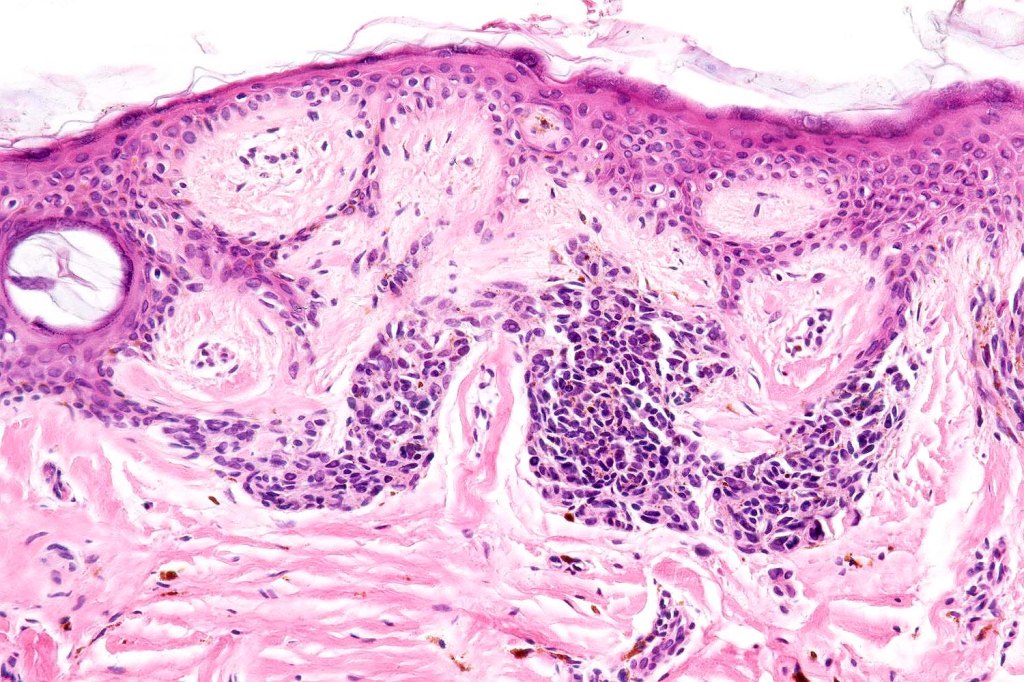

•Junctional/compound

•Large dyscohesive nests with retraction artifact, not restricted to the tips of the epidermal ridges

•Heavy pigmentation (sometimes gray/green)

•Bridging common, often over multiple rete ridges

•Variable atypia (can be marked)

•Central pagetoid spread

•Superficial dermal atypia